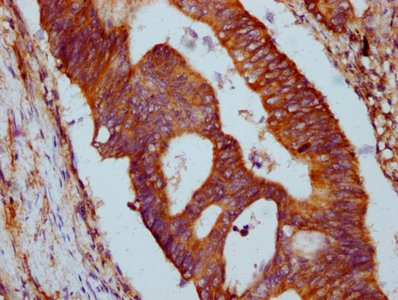

IHC image of CSB-PA769767LA01HU diluted at 1:500 and staining in paraffin-embedded human appendix tissue performed on a Leica BondTM system. After dewaxing and hydration, antigen retrieval was mediated by high pressure in a citrate buffer (pH 6.0). Section was blocked with 10% normal goat serum 30min at RT. Then primary antibody (1% BSA) was incubated at 4°C overnight. The primary is detected by a biotinylated secondary antibody and visualized using an HRP conjugated SP system.

IHC image of CSB-PA769767LA01HU diluted at 1:500 and staining in paraffin-embedded human colon cancer performed on a Leica BondTM system. After dewaxing and hydration, antigen retrieval was mediated by high pressure in a citrate buffer (pH 6.0). Section was blocked with 10% normal goat serum 30min at RT. Then primary antibody (1% BSA) was incubated at 4°C overnight. The primary is detected by a biotinylated secondary antibody and visualized using an HRP conjugated SP system.